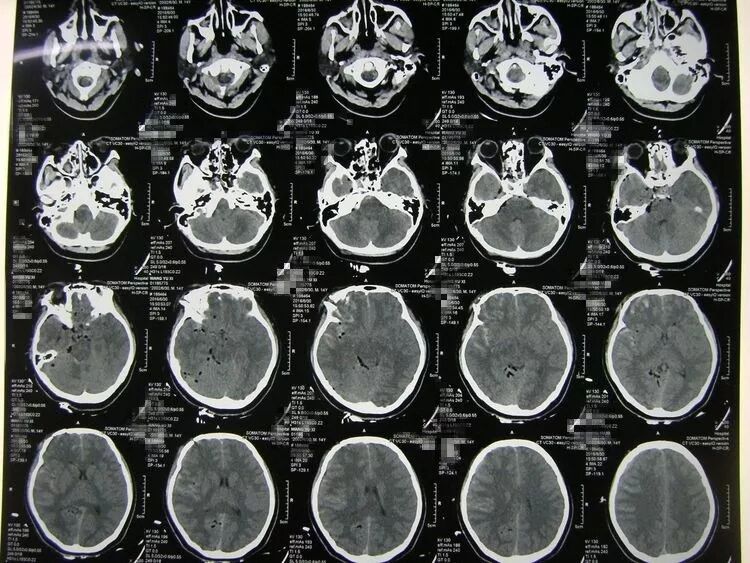

患儿男,16岁,头部等处车祸伤2小时入院,嗜睡状,左额颞顶处有数处头皮创口,颞顶处创口可见骨折内陷。

CT示:

额颞顶部硬膜外血肿,占位效应明显,局部颅骨粉碎骨折并内陷。

![]()

骨窗片显示额颞顶交界区骨折内陷并粉碎。